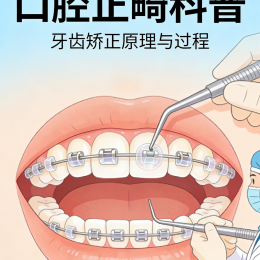

东莞正畸,矫正牙[详细]

东莞正畸,牙齿矫正[详细]